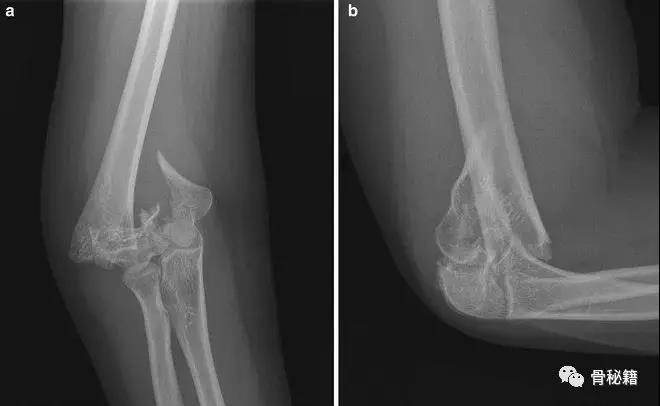

详细的术前评估

X线、CT、神经、等等